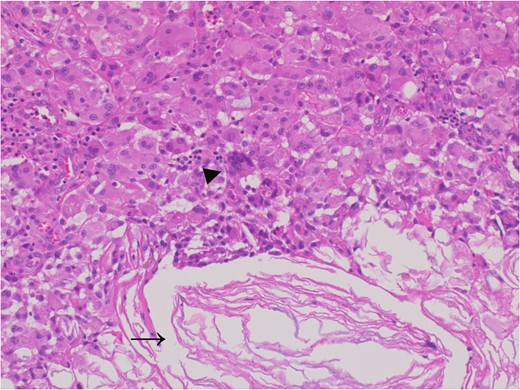

A 61-year-old man presented to the outpatient breast clinic with a painless lump in his right pectoral region. The lump was first noticed 40 years earlier at the size of a small fingertip and gradually increased. The lump was approximately 90 mm in diameter, well-defined, and dome-shaped. The overlying skin appeared glossy with no visible puncta (Fig. 1). Erythema or bruising was not observed. On palpation, the lump was non-tender and doughy with no localized temperature increase. It was not fixed to underlying tissue. On ultrasound imaging, the lump showed a hypoechoic and well-circumscribed oval mass containing variable echogenic foci and filiform anechoic areas without color Doppler signals (Fig. 2). The lump was located in the subcutaneous fat layer, with extensive dermal apposition. In sagittal magnetic resonance imaging (MRI), the lump showed a unilocular and well-defined cystic mass (70 × 40 × 90 mm) (Fig. 3A and B). The cyst content showed an isointense signal relative to the muscle with no enhancement in the sagittal enhanced T1-weighted image (Fig. 3A), and a hyperintense signal in the T2-weighted image (Fig. 3B). Ultrasound-guided percutaneous CNB was performed, and six core specimens containing cystic walls ware sampled (Fig. 4A). The cystic wall was lined with mature stratified squamous epithelium with a granular layer and did not contain an adnexal structure (Fig. 4B). In addition, many laminated or basket-woven keratin layers were sampled. These findings ware consistent with those of an epidermal cyst. The mass was excised under general anesthesia. The mass was well-defined and did not adhere to the surrounding structures, except for a portion of the CNB (Fig. 5). The mass was easily excised. The formalin-fixed mass was covered with a thick white fibrous capsule (Fig. 6A), which was filled with grey substances, such as bean curd residue, in the cross-section (Fig. 6B). After the removal of the contents, the internal surface of the capsule was crepey, and no nodules were observed (Fig. 6C). The definitive pathological diagnosis was an epidermal cyst without any malignancy. The adhesive region revealed keratin, which flowed outside the cyst, and a granulomatous response to keratin with multinucleated giant cells (Fig. 7). No complications or recurrences were observed during the one-year follow-up after surgery.

The adhesive region revealed keratin (allow) which flowed outside the cyst and granulomatous response for keratin with multinucleated giant cells (allow head), Hematoxylin and eosin stain, ×20 magnification.